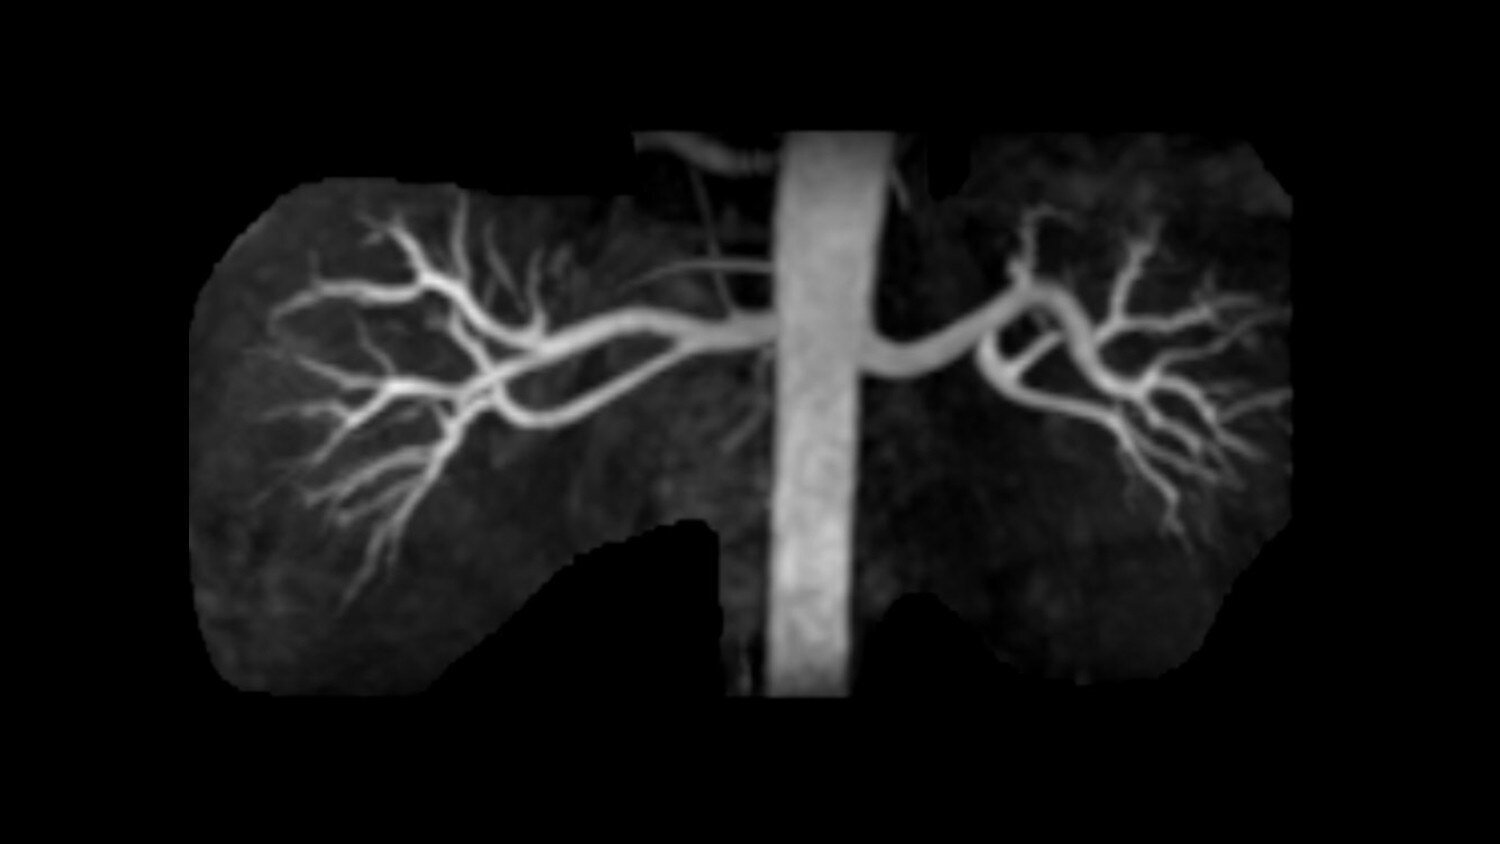

GEM Peripheral/Vascular Array - A high-density PV / lower extremity array that facilitates imaging of the thighs and lower legs with parallel imaging in all 3 planes. The coil incorporates an innovative self-supporting hinge design between the upper and lower elements to accommodate patients of various sizes with simplified set-up.

Its full 3.0T magnet and 70 cm bore work together to generate extraordinary image quality without compromises. The result for clinicians is new levels of diagnostic performance.

Intuitive applications help clinicians utilize the full potential of 3.0T MR imaging.